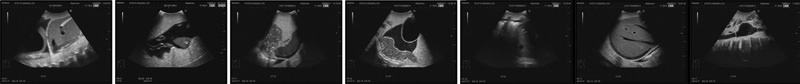

Die Abbildungen zeigen folgende Ultraschallbilder:

1. Herztamponade

2. Blutung im rechten oberen Abdomen

3. Blutung im linken oberen Abdomen

4. Blutung im Becken

5. Pleuraerguss

6. Perihepatische Blutung

7. Aortenaneurysma